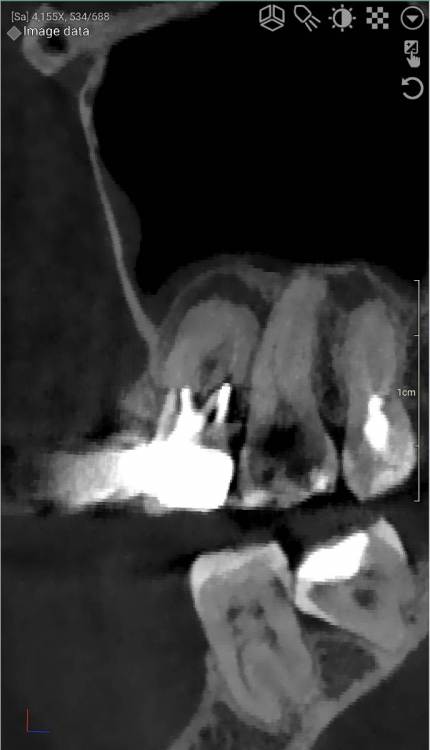

DeLaMer Опубликовано 11 августа, 2021 Поделиться Опубликовано 11 августа, 2021 (изменено) Добрый день уважаемым докторам-участникам форума. Хотелось бы, по возможности, получить экспертное мнение по поводу моей проблемы. На верхней челюсти есть мост, объединяющий 6й, 5й и отсутствующий 4 зубы (если я правильно понимаю нумерацию, это должны быть 24, 25, 26). В начале июня на десне открылся свищ с гноем (абсцесс, но, видимо, не острый, кроме периодического надувания гнойного шарика ничего больше не происходило). По этом поводу мой лечащий врач поднял КТ, которое было сделано осенью до того по другому поводу и обнаружила воспаление одного из корней 6-го зуба. При этом она высказала соображение, что может быть здесь поможет резекция верхушки того самого корня. Один из хирургов, с которым я консультировалась по этому поводу, сказал, что на его взгляд резекция возможна. Другой - что воспаление проявляется не только на одном корне, а на двух и по его мнению сделать тут ничего нельзя, только распиливать коронку и удалять 6й зуб. Я была бы крайне благодарна, если бы уважаемые специалисты высказали свое мнение по этому поводу, потому что при равноценных двух противоположных мнениях мне даже не понятно с чего начинать. Прикрепляю ссылку на файл КТ на своем дропбоксе. Огромное спасибо за помощь https://www.dropbox.com/s/fkv8cvqqq6grgpe/Sergeeva A..zip?dl=0 Изменено 11 августа, 2021 пользователем DeLaMer Ссылка на комментарий

Irouil Опубликовано 12 августа, 2021 Поделиться Опубликовано 12 августа, 2021 На мой взгляд тут резекция верхушки корня не поможет так как верхушка корня - далеко не единственная проблема этого зуба Ссылка на комментарий

Irouil Опубликовано 12 августа, 2021 Поделиться Опубликовано 12 августа, 2021 По представленным средам создаётся впечатление, что у зуба фактически разрушено соединение между корнями. Риски того, что он под нагрузкой раскроется в любой момент, достаточно высоки Ссылка на комментарий

АнтонТЛТ Опубликовано 13 августа, 2021 Поделиться Опубликовано 13 августа, 2021 (изменено) Там всё ок с фуркацией и вкладка коротконогая. Просто на КТ очень много артефактов. Изменено 13 августа, 2021 пользователем АнтонТЛТ Ссылка на комментарий